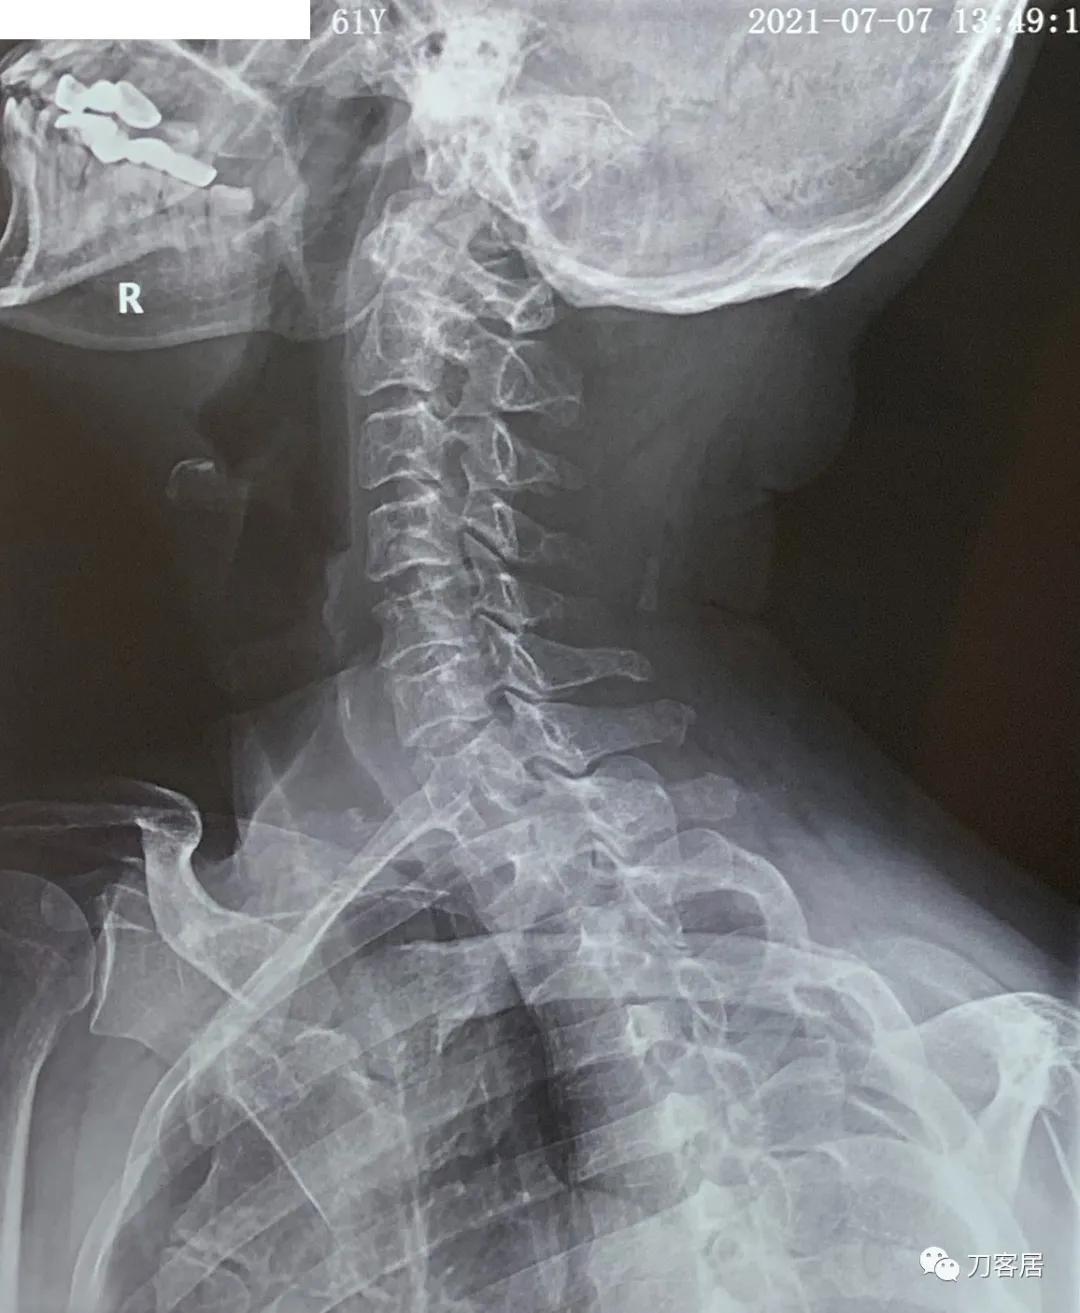

图12. 20210721颈椎过右斜位X线片,提示颈4-5,颈5-6椎间孔狭窄。